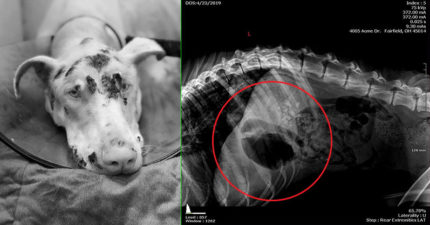

無良飼主「餓死愛犬」被判刑 照X光「裝滿巨石」網友:換他吃

世界, 動物